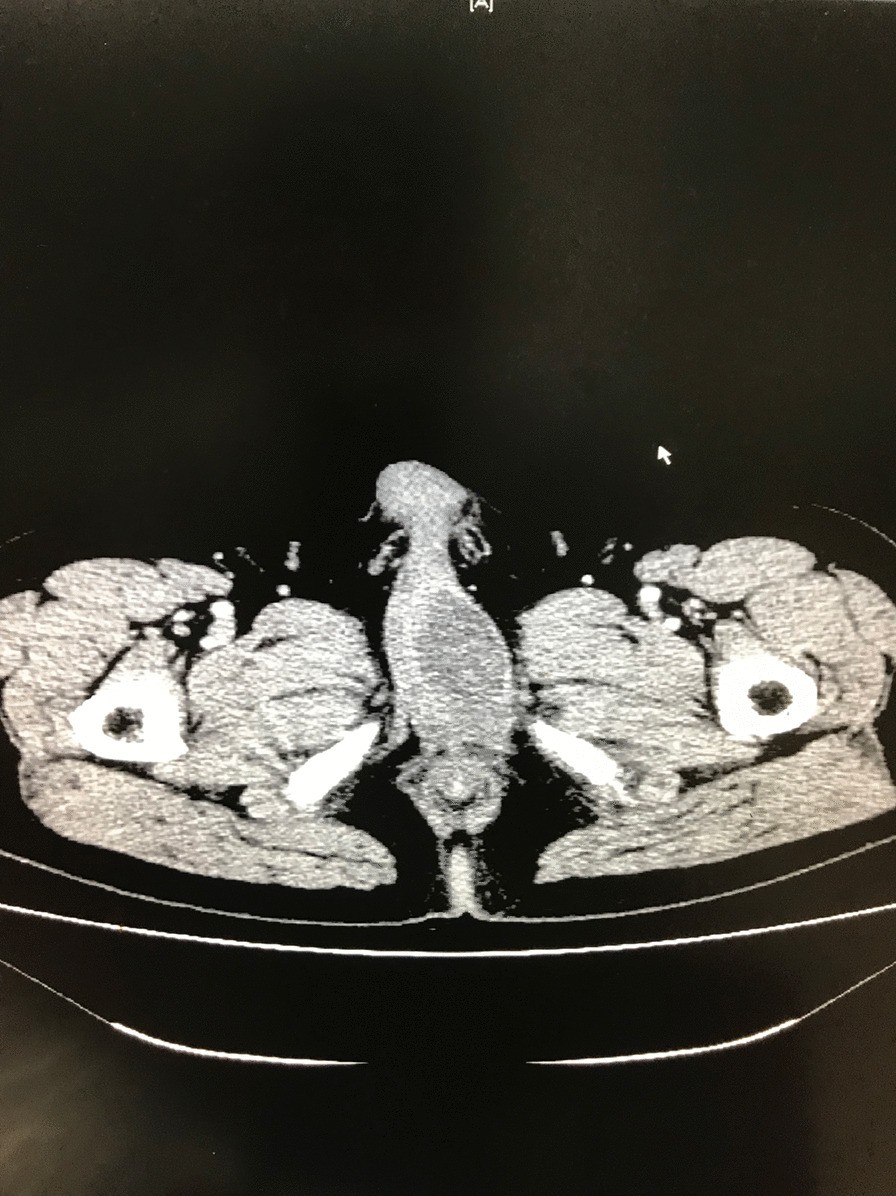

Computed tomography imaging. A well-defined, irregular, and heterogeneously enhancing soft tissue mass arising from the proximal part of the penis